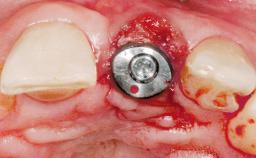

A 42-year-old female patient was referred to our clinic at the School of Dentistry of the University of São Paulo in November 2004, presenting a deficient restoration in the upper left central incisor. The clinical examination revealed no gingival retraction or any signs of gingival inflammation and, therefore, previous periodontal treatment was not considered. The patient presented a high lip line at full smile and a thin tissue biotype. This combination characterized a high-risk situation from an anatomic point of view, which required careful preoperative planning and cautious surgical execution.

Placement Protocol Immediate implant placement

Tooth Site Maxillary incisor or canine

Socket Morphology Single-root socket

Socket Integrity Sufficient, with intact bone walls

Bone Volume Sufficient, with intact walls